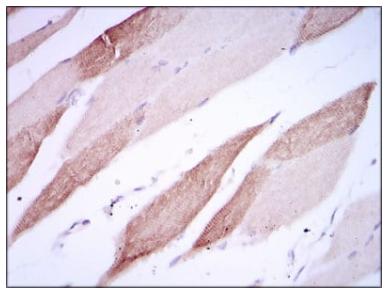

IHC    1/200 - 1/1000